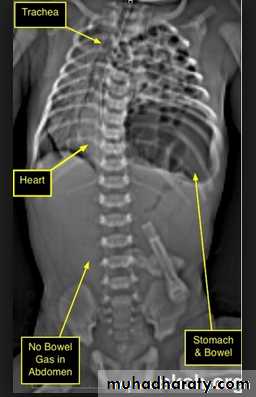

The plain film shows features which are typical for spinal tuberculous disease.

There is an extensive paraspinal soft-tissue mass.Detail in the underlying spine is poor but there is early crowding of ribs posteriorly, indicating early vertebral collapse.

(B) Coronal MR image of the thoracic spine demonstrates destruction of the intervertebral disc at the point where the paraspinal widening is maximal and this change is associated with alteration of signal from the vertebrae.